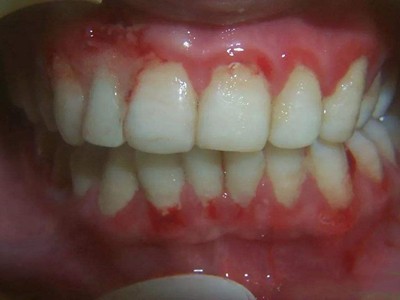

慢性龈炎又称边缘性龈炎或单纯性龈炎,主要表现为游离龈和龈乳头因炎性水肿,而变为鲜红或暗红色,龈缘变厚,龈乳头圆钝肥大。慢性龈炎的患病率高,治愈后仍可复发,部分患者可发展成为牙周炎。

慢性龈炎的病损部位一般局限于游离龈和龈乳头,以前牙区为主,尤其以下前牙区最为显著,患者常因刷牙或咬硬物时牙龈出血而就诊。游离龈和龈乳头颜色变为鲜红或暗红色,病变较重时炎性充血可波及附着龈。龈缘变厚,龈乳头圆钝肥大,可增生呈球状,覆盖牙面。牙龈松软脆弱,缺乏弹性。